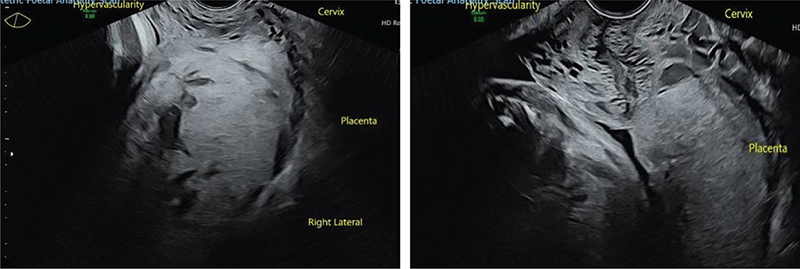

The image review also identified the potential misclassification of placental sonolucencies as lacunae rather than other benign placental cystic lesions in five out of the eight false-positive cases, albeit with the benefit of hindsight (Fig. 3). In three cases, the placental sonolucencies identified on ultrasound were more consistent with intra-placental lakes (centrally located, more regular in shape and widely spaced), and in two cases, more consistent with echogenic cystic lesions (well-circumscribed cystic lesions with a hyperechoic rim, often related to foetal growth restriction and pre-eclampsia). In the other three false positive cases, the appearance remained consistent with lacunae (irregularly shaped, located close to the placental bed), despite knowledge of the subsequent clinical and histopathological outcome.

JOGM-5-331-F3.jpg

Fig. 3. Types of placental echolucencies. Top left – focal lacunae in a case of accreta. Top right – diffuse lacunae (‘moth-eaten’ placenta) in a case of percreta. Bottom left – echogenic cystic lucencies (placental infarcts) in a false positive case of PAS. Bottom right – scattered benign intra-placental lakes in a false positive case of PAS.